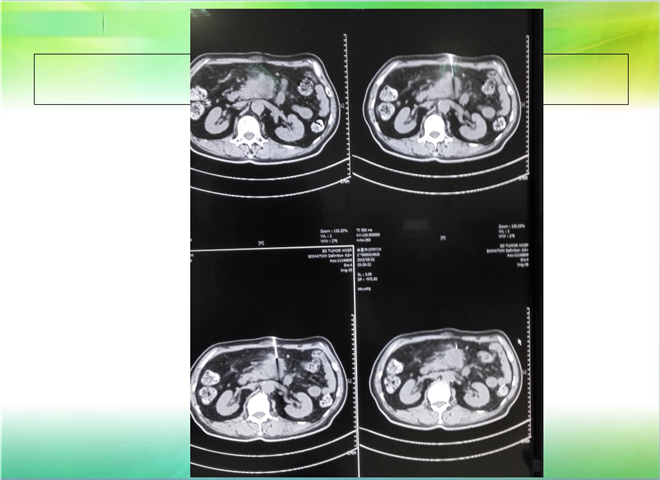

CT引导下穿刺活检术